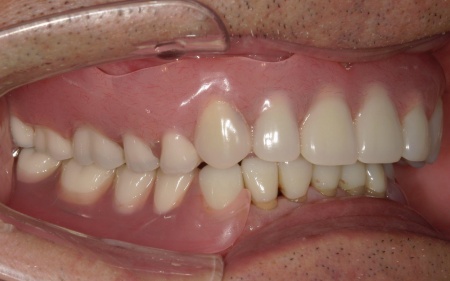

次に上下顎に装着するため、チタン床を使用した金属床義歯を作製しました。

チタンは軽量でありながら強度が高く、体になじみやすい特徴をもつ素材です。また、金属床にすることで従来の樹脂製義歯と比べて薄く作ることが可能になり、装着による違和感の軽減も見込めます。

また、上顎は残存歯が少ないためすべてを覆う総入れ歯で、下顎は前歯がしっかり残っているため部分入れ歯の形で作製しました。

完成した入れ歯を装着していただき、噛み合わせや義歯の安定性、見た目の仕上がりに問題がないことを確認して、治療を終了しています。